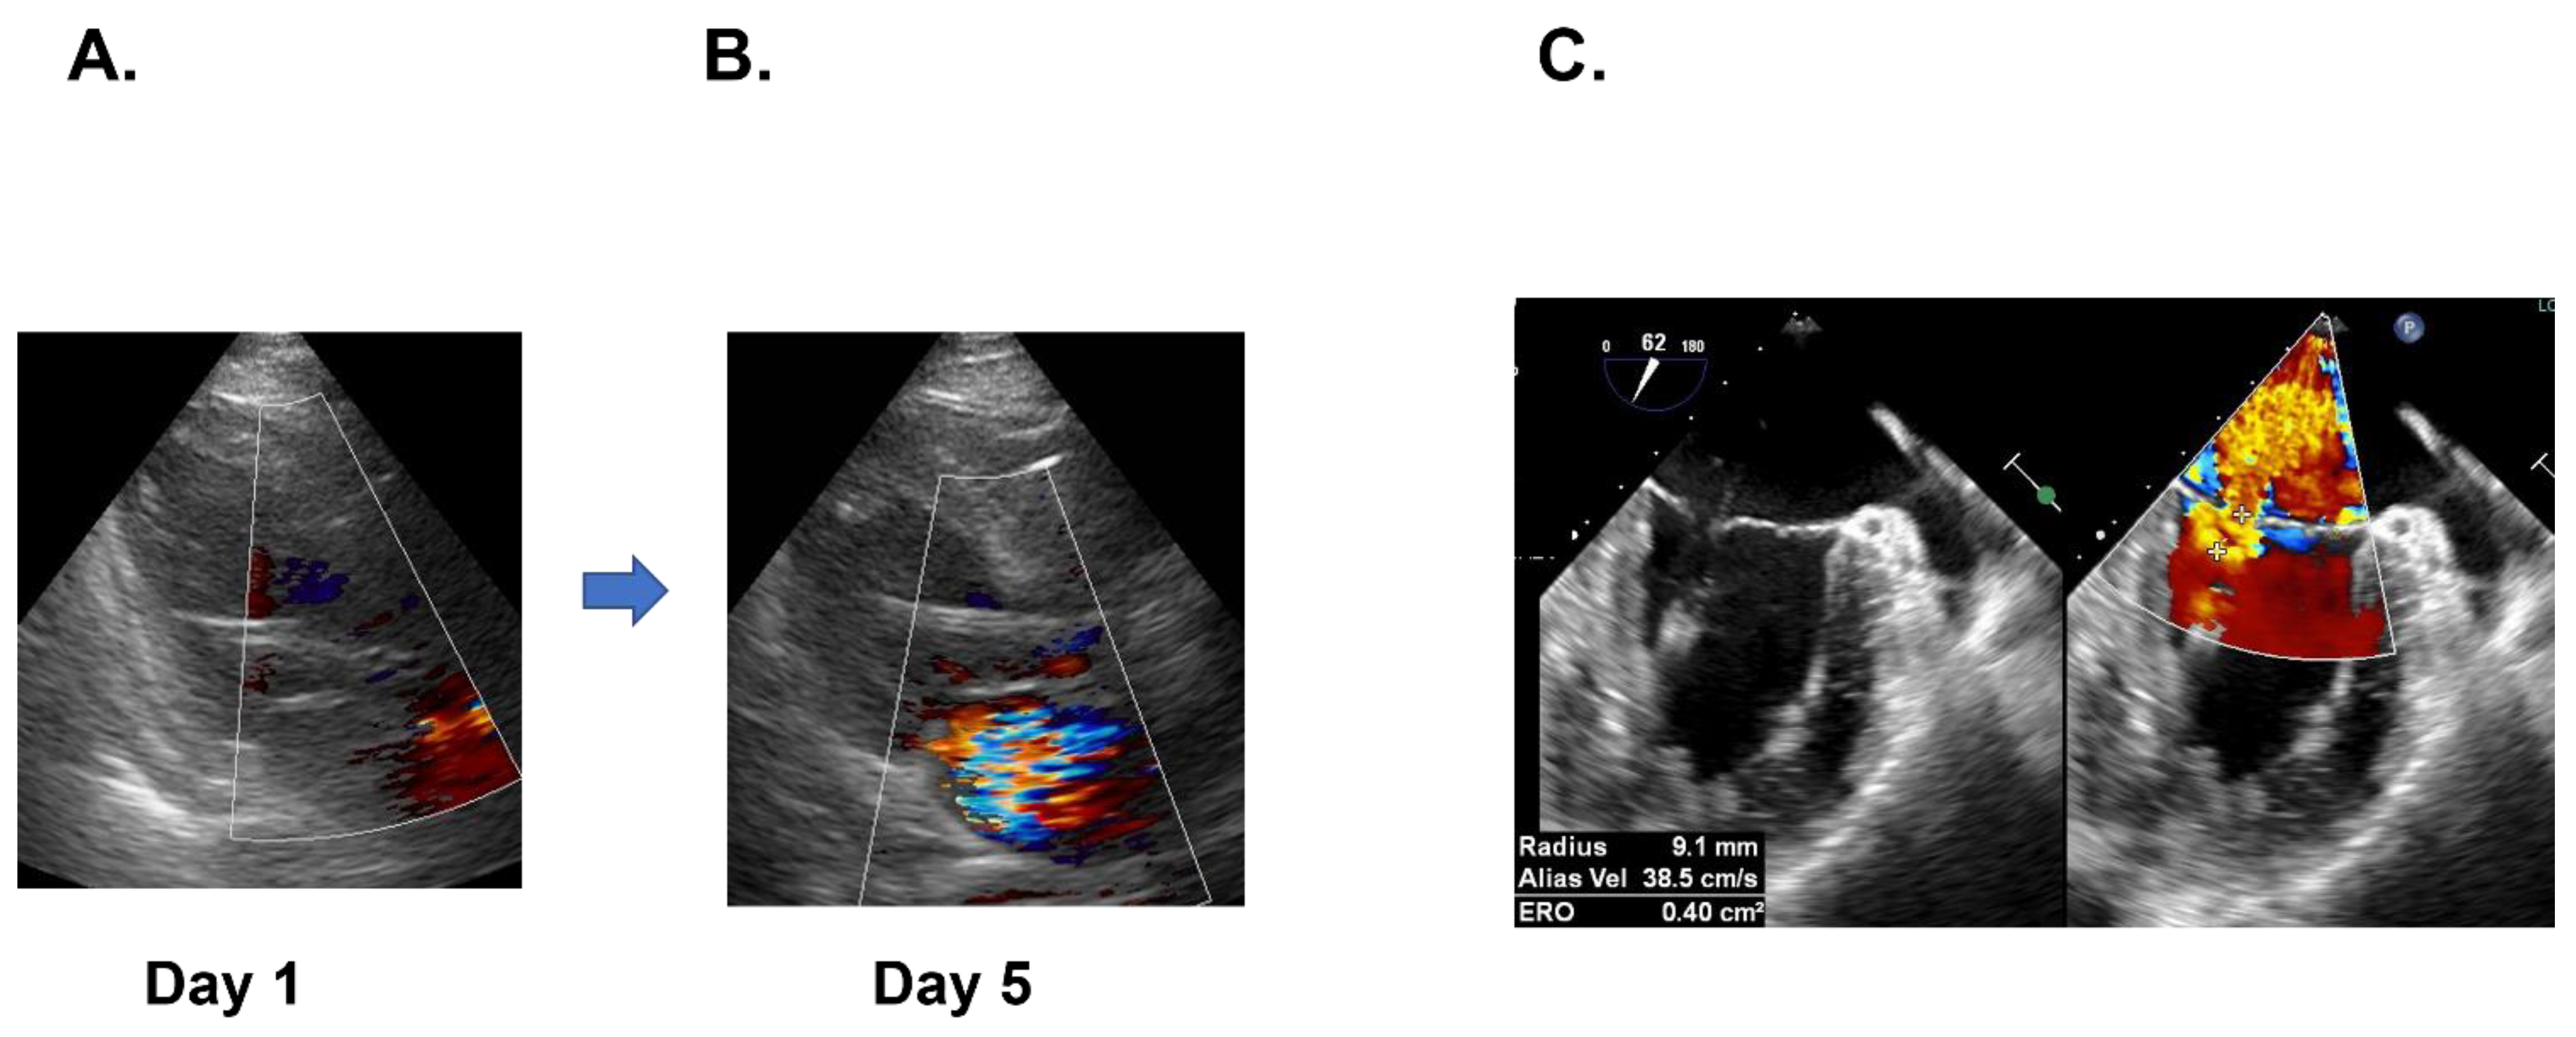

2.4. ECMO Weaning and Mitral Valve Replacement

3.3. Mitral Chordal Rupture and Mitral Valve Replacement